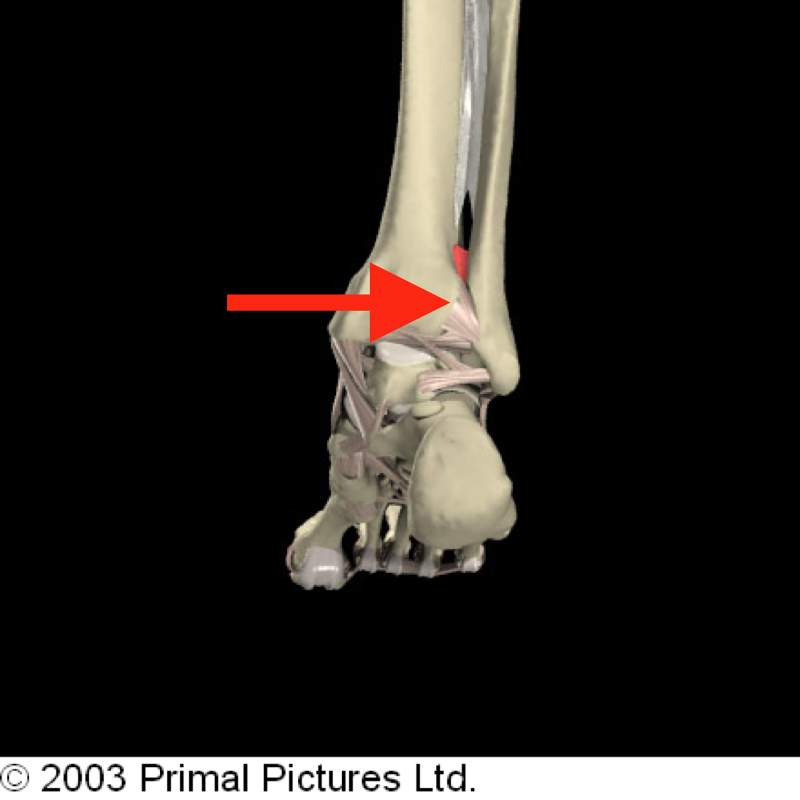

The syndesmotic articulation of the distal tibiofibular joint occurs between the convex surface of the distal tip of the fibula and the concave fibular notch of the distal tibia. The stability of the syndesmosis is crucial to proper dynamic ankle and lower extremity function.

It is formed between the distal tibia(concave surface) and fibula(convex surface), with no articular capsule or synovial membrane as a fibrous joint, and attached by the interosseous ligament (IOL), the anterior-inferior tibiofibular ligament (AITFL), the posterior-inferior tibiofibular ligament (PITFL), and the ...

This joint is located between the flat articular facet on the fibular head and a similar articular facet situated posterolaterally on the lateral tibial condyle. As expected, the superior tibiofibular joint is also surrounded by a joint capsule, which attaches to the margins of the articular surfaces of the fibula and tibia.

Articulating structures of superior tibiofibular joint

The articular surfaces of the superior tibiofibular joint include the following:

Joint capsule and ligaments

Both articular structures are surrounded by the fibrous joint capsule. Besides the capsule, this joint is strengthened with two ligaments - the anterior and posterior ligaments of the fibular head.

Which side of the body is the tibiofibular joint?

Lateral view of the tibiofibular joints on the right side of the body.

Where is the syndesmosis fibrous joint located?

This is a syndesmosis fibrous joint located between the medial side of the lateral malleolus of the fibula and the fibular notch of the distal tibia.